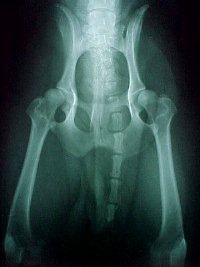

Here are a few examples of hip evaluation IN BEAGLES from OFA.

As you look at these pictures, try to imagine the angle, the smoothness and length of femur neck and the roundness of the femoral head.  Draw two imaginary lines, one from the top rim of the acetabulaum to the outer edge and another line depicting the angle.

OFA EXCELLENT

OFA GOOD

OFA FAIR

OFA MILD HD

Note

1. the subluxation and the shallow acetabulum

2. the rim changes on the upper point of the acetabulum rim

3. the decreased angle of the femoral neck

4.